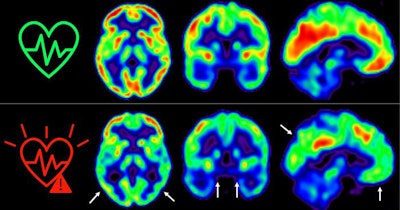

The image represents glucose uptake in the brain measured by positron emission tomography in middle-aged individuals with low (top) or high (bottom) sustained cardiovascular risk over five years. The colors represent cerebral glucose consumption, with red indicating higher consumption and blue lower consumption. Image courtesy of the Spanish National Center for Cardiovascular Research in Madrid (CNIC).According to the analysis, a persistent high risk of cardiovascular disease was associated with an accelerated decline of cortical F-18 FDG uptake compared with low-risk individuals. Specifically, on average, standard uptake value ratios (SUVRs) decreased by 61% per year in the whole cortex and by 77% per year in hypometabolic regions associated with Alzheimer's disease.

"Our results show that asymptomatic middle-aged individuals at high risk of cardiovascular disease over a five-year period have a steeper decline in cerebral glucose metabolism compared with individuals at low risk," the authors wrote.